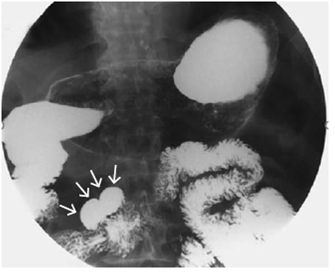

Para continuar con el estudio, se usó una cápsula endoscópica para buscar sangrado oculto manifiesto, la cual demostró una probable lesión en la segunda porción del duodeno (figura 2). Por esta razón, se practicó una tercera endoscopia de vías digestivas altas que evidenció un divertículo duodenal y una duplicación duodenal tubular, sin alteraciones de la mucosa (figura 3). En las vías digestivas altas se evidenció una duplicación tubular del duodeno en su tercera porción (figura 4).